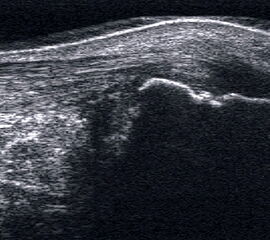

Impingement bei osteophytären Anbauten an der ventralen Tibia und am Talushals.

Abbildung 51

Lagerung: Rückenlage.

Schnittführung: Ventraler LS und TS über dem OSG.

Referenzstrukturen: Distale Tibia, Innenknöchel und Talusrolle.

Befunde: Beim knöchernen Impingement finden sich an der distalen Tibia und Talusrolle besonders in den Insertionsarealen der oberflächlichen Anteile des Deltabands echogene osteophytäre Ausziehungen, die hier nicht Folge einer Arthrose sind, sondern zugbedingte Verkalkungen ventromedialer Kapselbandanteile (Fußballer-Sprunggelenk) (Abb. 51). Bei maximaler Dorsalextension kann ein Kontakt dieser Sporne im Sinne eines knöchernen Impingement zu beobachten sein.

Beim Weichteilimpingement kommt es fibularseitig zu Einklemmungserscheinungen (Meniskoid), die jedoch nicht sonographisch darstellbar sind. Auch das dorsale knöcherne Impingement des oft degenerativ ausgezogenen Proc. posterius tali (Nußknackereffekt) oder bei einem mobilen Os trigonum ist nicht sonographisch darstellbar.